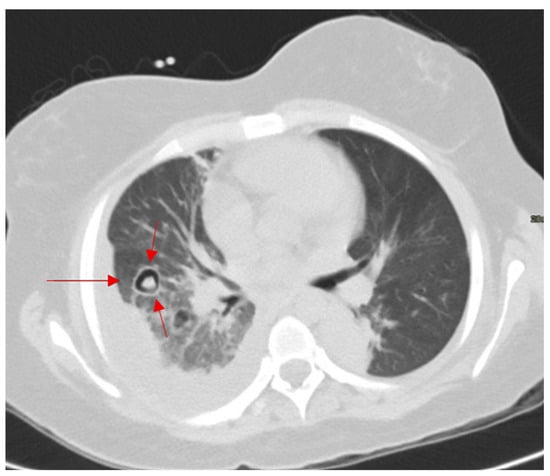

Cosmic Signs in Radiology: A Pictorial Review

Pattern recognition remains a cornerstone of radiologic interpretation, as it facilitates a confident and comprehensive differential diagnosis. Certain pathologies present with specific and highly recognizable patterns on imaging modalities. These patterns can resemble familiar real-life phenomena, including cosmic bodies that surround us. We present in this article a compilation of radiologic signs across various modalities that take inspiration from cosmic phenomena. For each sign, we summarize its defining imaging appearance, typical clinical context, and common pitfalls; where available, we note diagnostic performance (e.g., sensitivity/specificity) to guide appropriate weighting in practice. By coupling memorable imagery with succinct clinical guidance, this pictorial review aims to support a faster, more accurate pattern recognition that is applicable in both low-resource and tertiary care settings, while recognizing that these signs function as educational aids rather than validated diagnostic tests. In familiarizing themselves with these classic signs, training radiologists can benefit from an engaging and memorable way of recognizing various pathological conditions. Full article

Figure 1